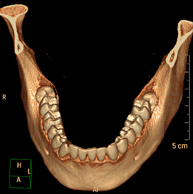

- TC Macizo facial

Prueba radiológica que consiste en obtener imágenes del macizo facial (cara) de alta definición anatómica mediante el empleo de un equipo de TC (Tomografía Computarizada). Indicaciones: tumores, cirugía plástica.

- TC Dental

Prueba radiológica que consiste en obtener imágenes de los huesos maxilares de alta definición anatómica (piezas dentarias, trayecto del nervio dentario), mediante el empleo de un equipo de TC (Tomografía Computarizada). Indicaciones: estudio previo a la extracción dental, estudio previo a implantes, tumores, absceso.